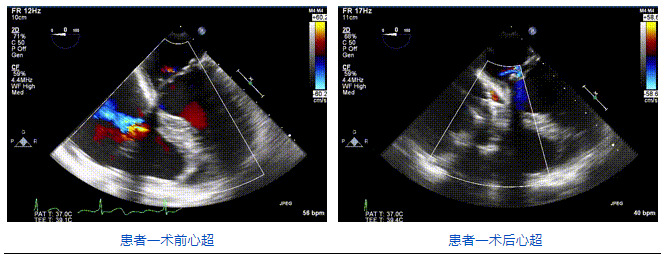

2021年12月24日,復(fù)旦大學(xué)附屬中山醫(yī)院葛均波院士團(tuán)隊(duì)成功應(yīng)用LuX-Valve Plus為一例極重度三尖瓣反流(TR)合并房顫、房缺的患者完成了經(jīng)血管三尖瓣置換術(shù),這是在前基礎(chǔ)上,本周完成的第三例經(jīng)血管三尖瓣置換手術(shù),葛均波院士、周達(dá)新教授等與心外科魏來(lái)教授、賴顥教授,心超室的潘翠珍教授、李偉教授及麻醉科的郭克芳教授共同完成了本周手術(shù),均獲得圓滿成功!患者術(shù)后超聲顯示無(wú)TR,臨床癥狀明顯改善。本周手術(shù)的成功也為L(zhǎng)uX-Valve Plus救治性臨床研究添上了濃墨重彩的一筆。

三例患者入院后,葛均波院士團(tuán)隊(duì)周達(dá)新教授、潘文志教授、張?jiān)床┦?、陳莎莎博士及心超室的潘翠珍教授、李偉教授?duì)患者的情況進(jìn)行詳細(xì)評(píng)估和討論,最終決定為三例患者選擇LuX-Valve Plus40mm、50mm和50mm型號(hào)的瓣膜進(jìn)行手術(shù)治療。手術(shù)后即刻拔除氣管插管,術(shù)后患者三尖瓣反流癥狀得到顯著改善,復(fù)查心超結(jié)果顯示人工三尖瓣瓣膜支架固定穩(wěn)定,瓣葉關(guān)閉形態(tài)未見異常,未見明顯反流。